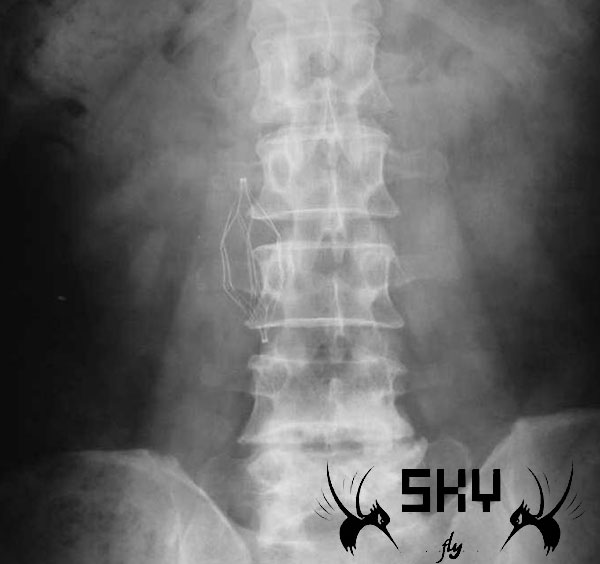

Home / Surgical Dep / 先健Aegist滤器置入和取出手术

下腔静脉滤器对于大家来说并不陌生,在这里和大家分享一个下腔静脉滤器的释放和取出的操作视频,希望对大家有所裨益。视频播放密码为sky